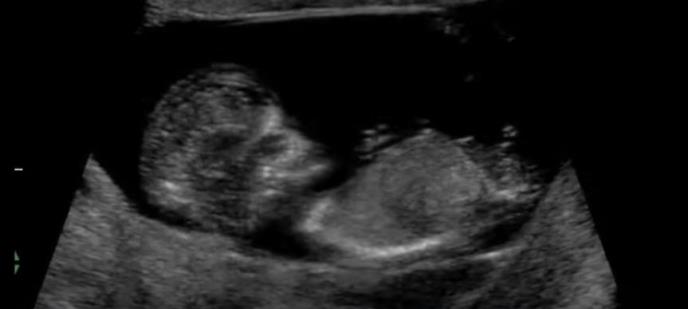

Na Jutjubu je osvanuo snimak koji prikazuje razvoj bebe u stomaku i oduševio je mnoge koji su se pitali kako se tačno odvija čudo stvaranja novog života.

Na videu je proces rasta bebe tokom svih 9 meseci, a kadrovi su neverovatni, pa je snimak pogledan čak 33 miliona puta.